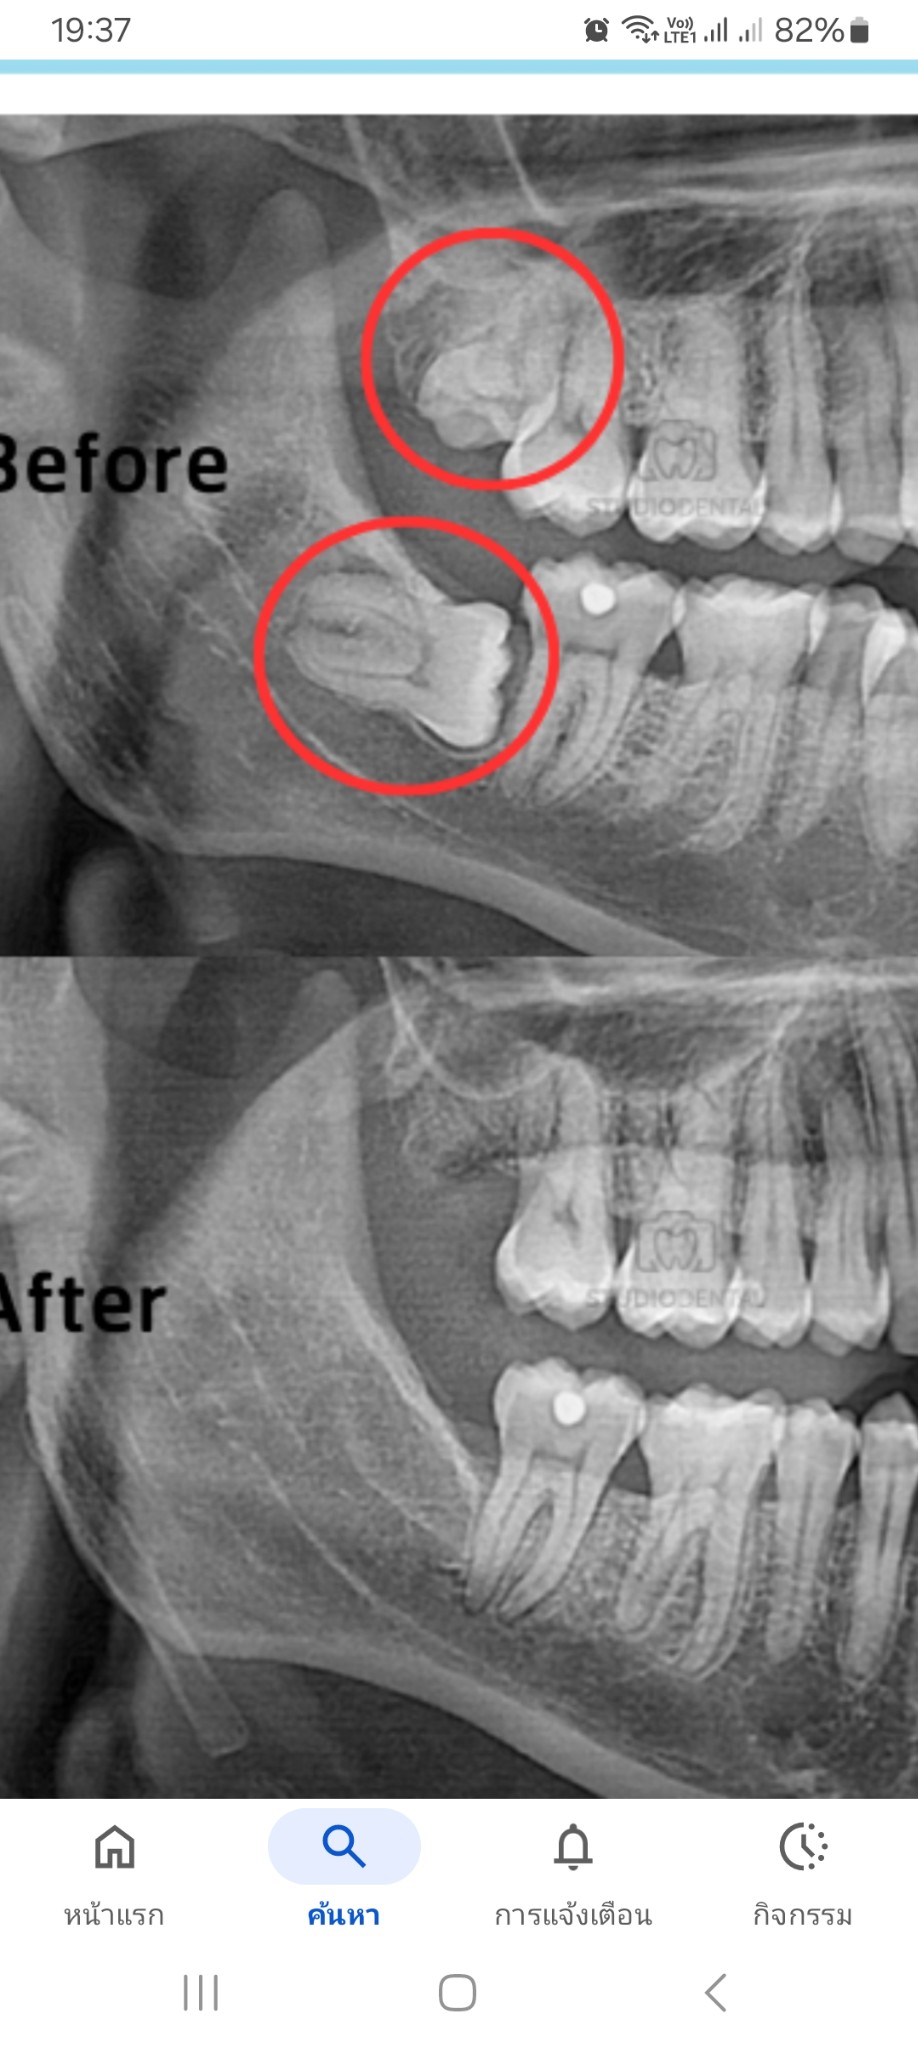

ถ้าฟันคุดนอนแบบนี้ ผ่ายากไหมคะ ราคาประมาณเท่าไหร่คะ

ฟันคุด